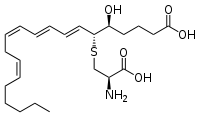

Leukotrienes pathway

Leukotrienes are synthesized in the cell from arachidonic acid by 5-lipoxygenase. The catalytic mechanism involves the insertion of an oxygen moiety at a specific position in the arachidonic acid backbone. The lipoxygenase pathway is active in leukocytes, including mast cells, eosinophils, neutrophils, monocytes, and basophils. When such cells are activated, arachidonic acid is liberated from cell membrane phospholipids by phospholipase A2, and donated by the 5-lipoxygenase-activating protein (FLAP) to 5-lipoxygenase. 5-Lipoxygenase (5-LO) uses FLAP to convert arachidonic acid into 5-hydroperoxyeicosatetraenoic acid (5-HPETE), which spontaneously reduces to 5-hydroxyeicosatetraenoic acid (5-HETE). The enzyme 5-LO acts again on 5-HETE to convert it into leukotriene A4 (LTA4), an unstable epoxide. In cells equipped with LTA4 hydrolase, such as neutrophils and monocytes, LTA4 is converted to the dihydroxy acid leukotriene LTB4, which is a powerful chemoattractant for neutrophils acting at BLT1 and BLT2 receptors on the plasma membrane of these cells. In cells that express LTC4 synthase, such as mast cells and eosinophils, LTA4 is conjugated with the tripeptide glutathione to form the first of the cysteinyl-leukotrienes, LTC4. Outside the cell, LTC4 can be converted by ubiquitous enzymes to form successively LTD4 and LTE4, which retain biological activity. The cysteinyl-leukotrienes act at their cell-surface receptors CysLT1 and CysLT2 on target cells to contract bronchial and vascular smooth muscle, to increase permeability of small blood vessels, to enhance secretion of mucus in the airway and gut, and to recruit leukocytes to sites of inflammation. Both LTB4 and the cysteinyl-leukotrienes (LTC4, LTD4, LTE4) are partly degraded in local tissues, and ultimately become inactive metabolites in the liver.